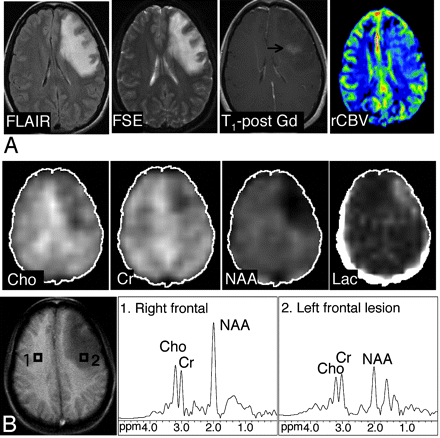

The accompanying table shows average metabolite ratios and rCBV in tumors and nonneoplastic lesions. Examples of spectra, metabolite images, and CBV maps of a tumor and proved benign lesion are shown in Figs 1 and 2, respectively.

Axial FLAIR, T2-weighted FSE, contrast-enhanced T1-weighted SE MR images and axial CBV map in a 27-year-old woman with meningoencephalitis. There is an abnormal high T2 signal intensity in the left frontal lobe with minimal enhancement on the postgadolinium image. The CBV map shows slightly elevated levels of blood volume in the lesion compared with the normal contralateral side, with a rCBV of 1.35. The original diagnosis on the basis of conventional MR imaging favored a neoplasm over an inflammatory cause. At 3 weeks of follow-up (MR spectroscopy was not performed), an overall improved appearance with a decrease in the size of the frontal subcortical and deep white matter T2 signal intensity abnormality was noted. A, B, The abnormal signal intensity of the lesion extended over 5 FSE sections (5-mm section thickness, no gap; with 2 sections showing the bulk of the lesion). One MRSI section (the bottom section shown in the figure) covered the lesion. Images of the Cho, Cr, NAA, and lactate metabolites and proton MR spectra of the lesion (voxel 2) and control region (voxel 1) are shown. The NAA/Cho ratio of 1.15 was above the cutoff point of 0.61, Chonorm was 0.8, and rCBV was slightly below the cutoff point of 1.5. On the basis of MRSI and perfusion MR imaging, the presence of a nonneoplastic lesion was favored. Discriminant function analysis classified this lesion as nonneoplastic on the basis of MRSI data alone and MRSI and perfusion MR imaging data.